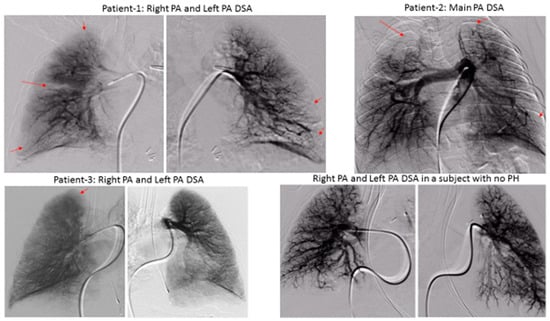

Our DSPA technique used digital images to perform “instant” subtraction, contrast enhancement, and pixel shifting [5]. The first image (the mask) was obtained without the contrast; successive images were obtained after injecting 1 ml/kg of the contrast (1:2 diluted) through an angiographic catheter in the pulmonary artery, and then images were acquired at a rate of 15 frames/sec. Respiration was suspended for the duration of the angiogram. The mask image was digitally subtracted from the successive contrast images automatically using dynamic masking and the time-interval-difference mode, which rendered the contrast filled vessels free of background details and blurred the non-opacified cardiac outline. This mode displays the differences between the two successive images (i.e., frame 2 minus frame 1, frame 3 minus frame 2, and so on). The image processor is the heart of DPSA because it is the part of the system where subtraction and image enhancement takes place. A general flow of information in the DPSA system is shown in Figure 1.

Figure 1.

Flow of information in a generalized digital subtraction system.